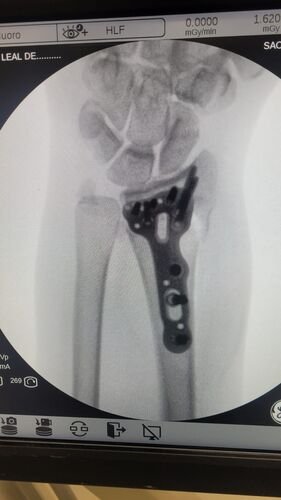

Meu nome e Isabella, mais conhecida como Snow, eu estava andando de muleta e a borracha dela saiu e eu tenho problema de equilibrio devido ao meu femur, bati o osso e piorou a situação, tive o radio do braço afetado e colocaram pino e deram um jeito de reverter porque eu ficaria com movimento do braço e mão comprometidos, tive traumatismo craniano porque bati a cabeça, esse ano eu já tinha sofrido um depois de um aparelho de raio x cair na testa mas fiquei sem sequelas na cabeça. Bom como muitos que me acompanham eu tenho uma condição rara entre mulheres que eu tenho os ossos do fêmur necrosados em mais de 75% desde 2022, eu sofri um acidente hoje andando de muleta, machuquei o fêmur, rosto, tivd que operar porque era uma emergência, não tenho muitas fotos pois estava internada mas tentei no SUS e não tinha pino de titânio,meu caso era de extrema urgência, eu to vendendo tudo e abrindo mão ate do meu apartamento pra cobrir a cirurgia e tenho ate final de setembro pra bater pelo menos 20 mil de meta, tenho inúmeras vakinhaa mostrando minha real doença autoimune e uma delas sendo rara que é osteonecrose bilateral do fêmur, o tratamento tá sendo todo particular mesmo sendo paciente do hospital das clínicas, ainda e difícil e nem sempre consigo as coisas, eu tento de todas formas é isso ainda pode me prejudicar na minha carreira, detesto pedir ajuda mas não tenho opção, a comunidade da minha área entre outros interesses sempre me apoiaram e infelizmente veio com humildade e de cabeça baixa pedir ajuda, faz tempo que tento recomeçar minha carreira desde o diagnóstico e nunca desisti dos meus sonhos e cirurgia

Vou deixar imagem atual do acidente abaixo e de algumas vakinhas anteriores